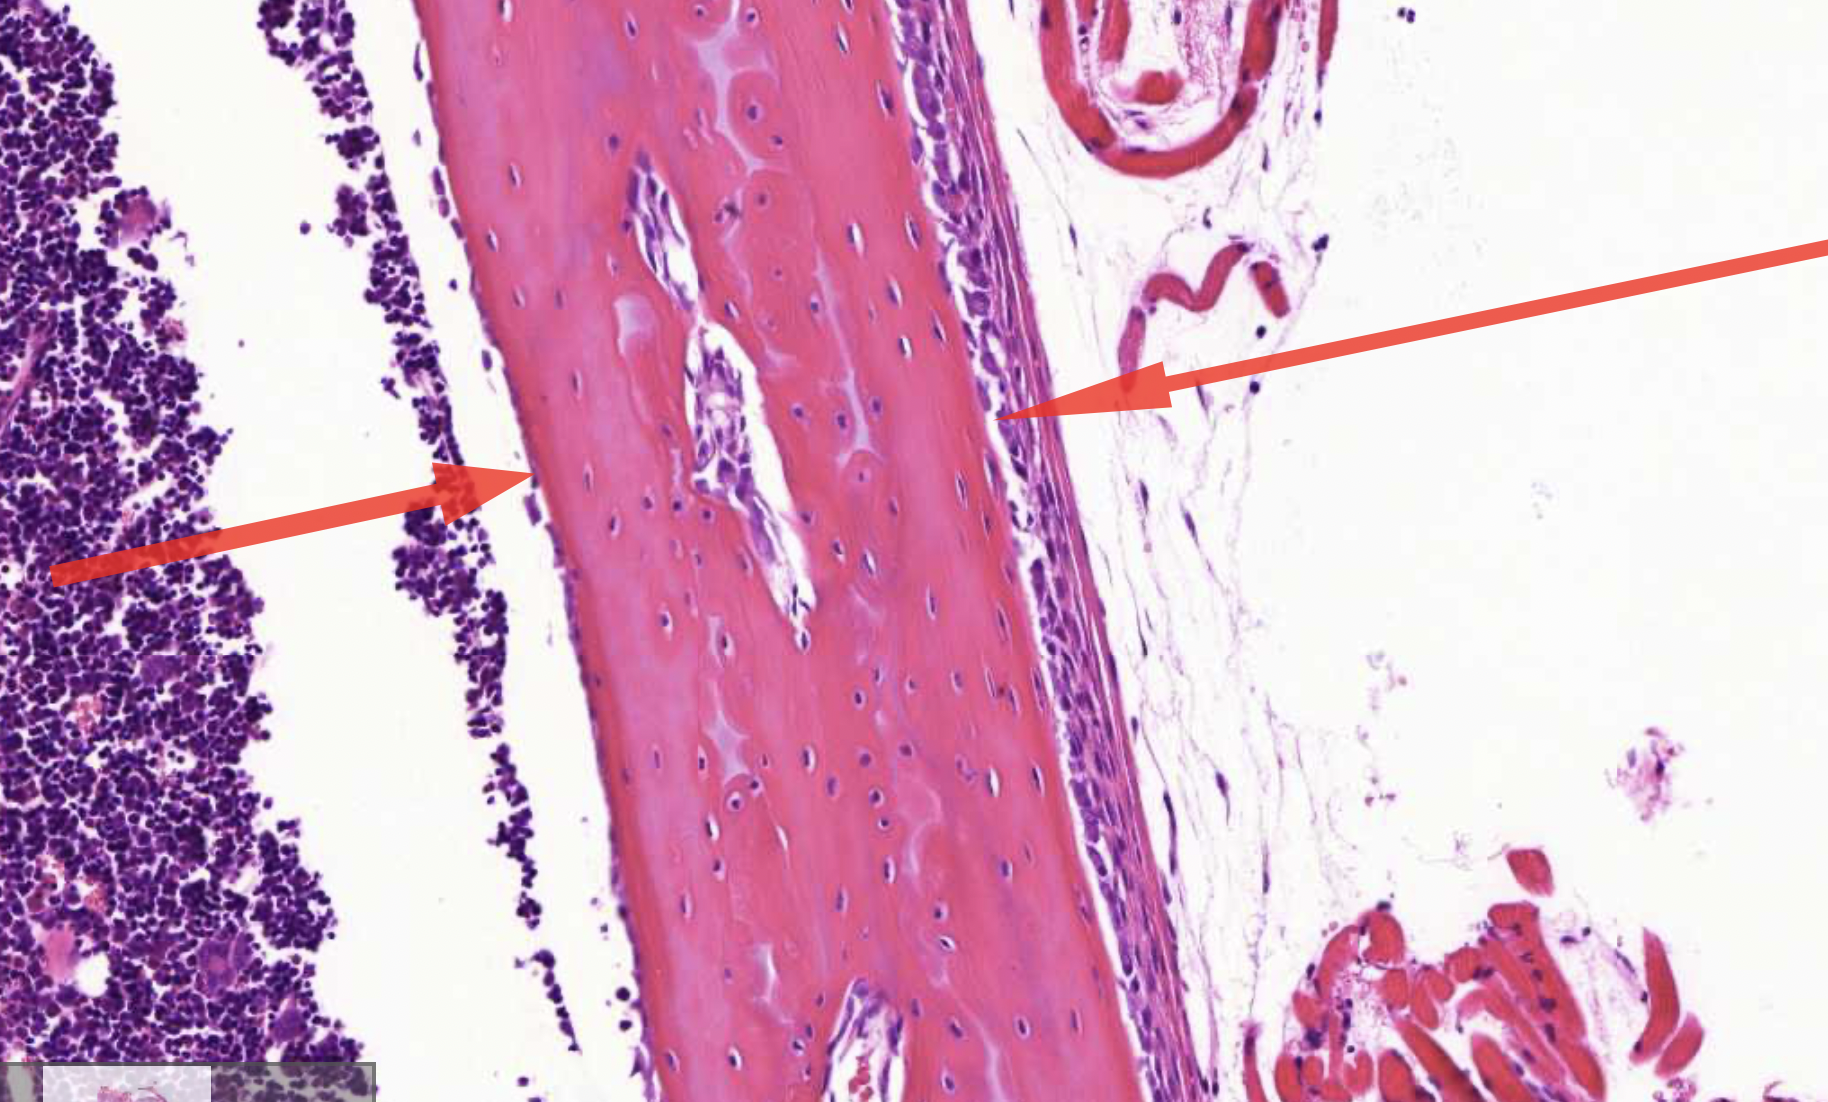

term image

• endosteum - inside or cortical bone

• peristeum - outside or cortical bone